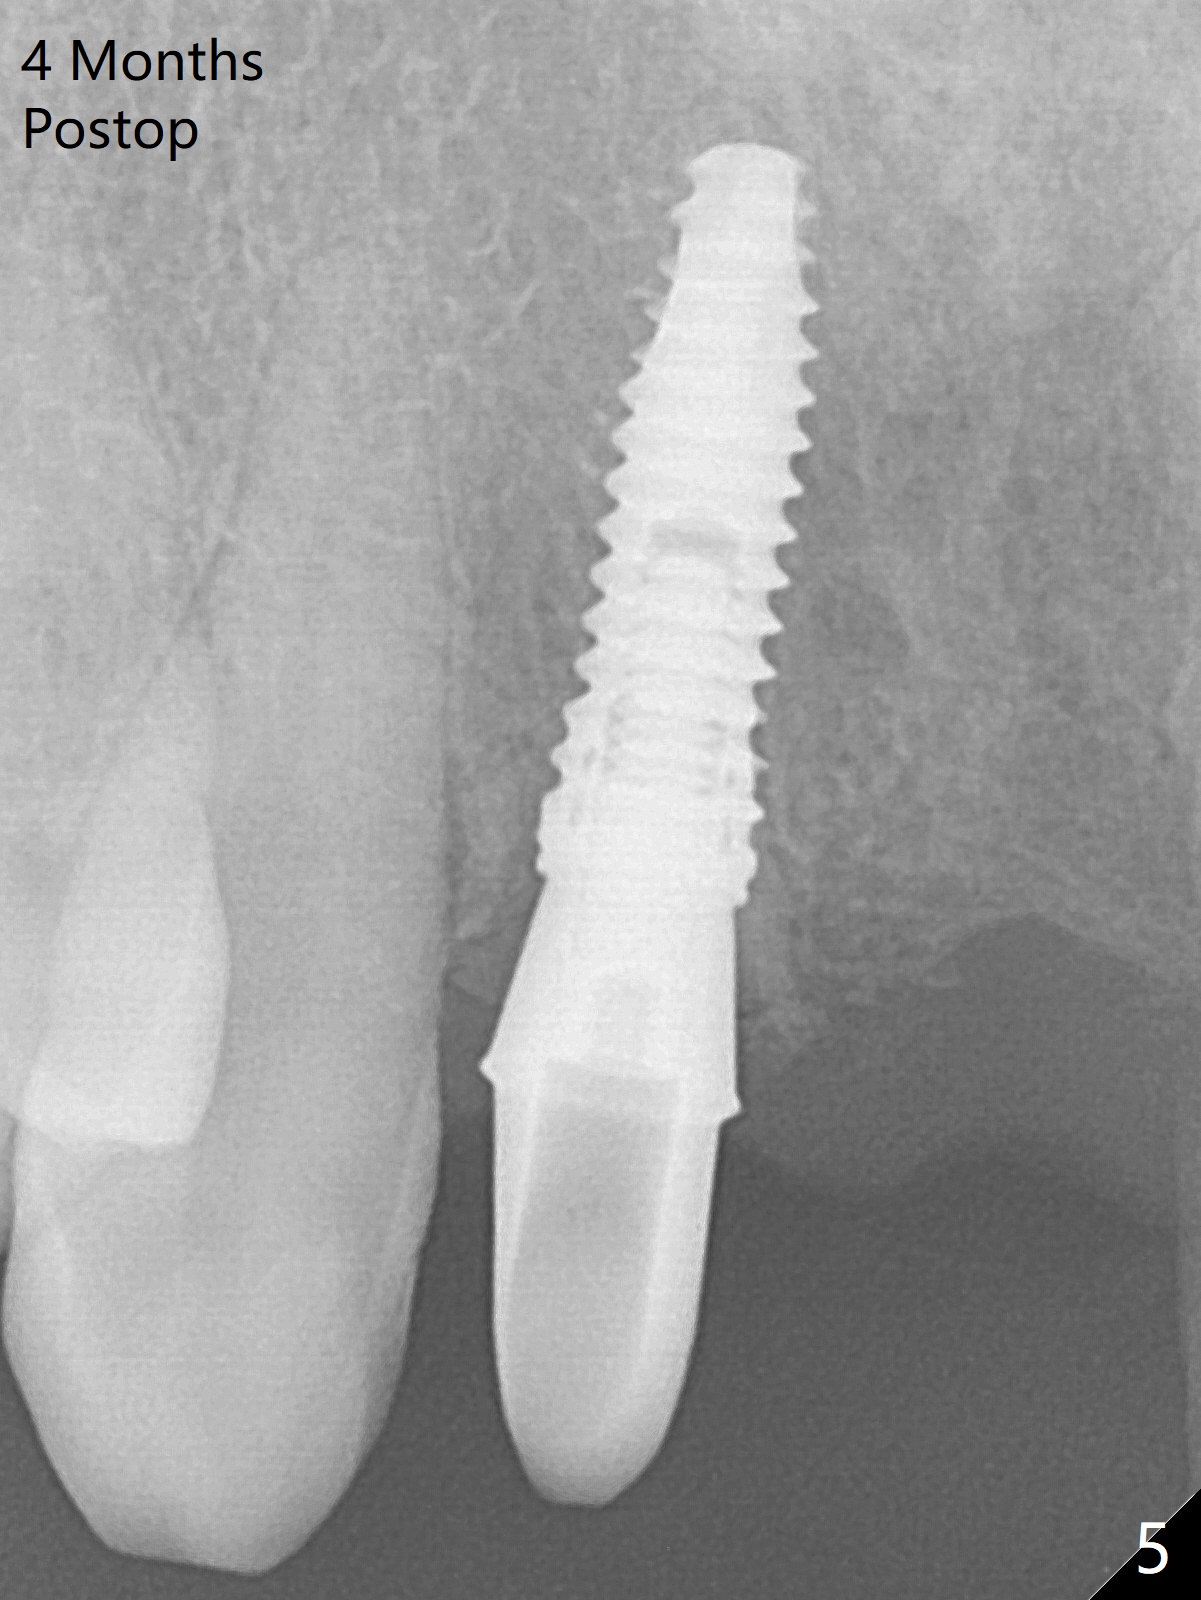

Since the pontic (Fig.1 #8) of the existing failed FPD has severe buccal concavity (*), socket shield is performed when #7 and 9 are extracted (Fig.2,3 *). Angled abutments are placed when 3.5x13 mm implants are inserted with guide. An immediate provisional FPD is fabricated. Acrylic is added to the pontic of the temporary FPD (Fig.4 arrow) to form a concave pontic gingiva (blanch)16 days postop. The patient returns 3.5 m postop with concern over temp being bulky and turning yellow. With Cetacaine and 1-0 cord, labial reducion is done for 7,9 abutments as well as 7 incisal reduction. The provisional is relined to increase 7 8 crown length. Next visit we will continue modification of temporary. Photos will be taken before and after modification (buccal and incisal views). The patient complains of occasional pain at #7. Check whether the socket shield at #7 is a culprit. In fact the implant at #7 is normal. Manipulation of the provisional does not help cosmetics much. A permanent restoration is delivered 5.5 months postop (Fig.7-9).